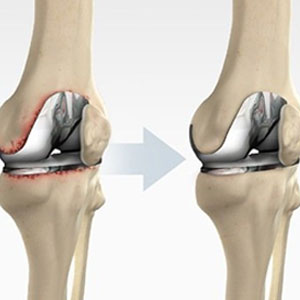

Total knee replacement is one of the most successful procedures in all of medicine...

Read details